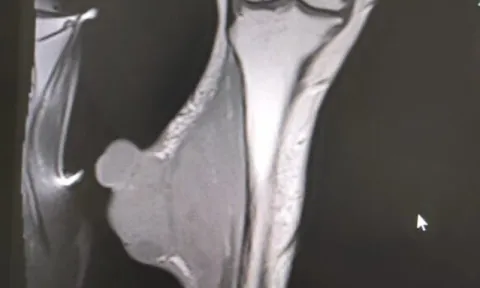

Thấy “vảy ốc” ở chân, người phụ nữ đi khám phát hiện ung thư di căn

Khi có các dấu hiệu tổn thương, những bất thường trên cơ thể, người dân không nên chủ quan.